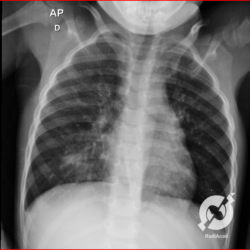

E o nome dado a esta alteração radiográfica que corresponde à substituição do ar alveolar por líquido é a consolidação alveolar.

Uma consolidação alveolar é, por definição, uma opacidade (imagem densa, branquinha) homogênea ou às vezes heterogênea (pela presença de calcificações ou cavidades), de limites mal definidos, exceto quando toca a pleura da parede ou das cissuras pulmonares. É um termo usado tanto em radiografia, como em tomografia computadorizada. Na tomografia, um outro termo é usado: vidro fosco, que é uma opacidade (branquinha mas não tanto como a consolidação), que borra o pulmão mas deixa ver os vasos de permeio (igual bigode de adolescente: dá pra ver todo o fundo).

Nós vamos mostrar aqui um pequeno apanhado de pneumonias de variados agentes, em diversos segmentos e lobos pulmonares, com extensões variadas. O objetivo é identificar o padrão radiológico de consolidação alveolar e não determinar o agente infeccioso, isso vai ser assunto para mais adiante. Aliás já antecipo que é fundamental saber localizar a lesão, porque alguns destes bichos gostam de determinados segmentos, alguns tumores também têm as suas preferências, então localização é fundamental. Se localização não fosse importante, um apartamento na beira do mar sairia o mesmo preço de um apartamento de frente pra BR-101, concordam?

Seguem alguns dos nossos casos de pneumonia para vocês treinarem os olhos e não se apavorarem nos plantões.